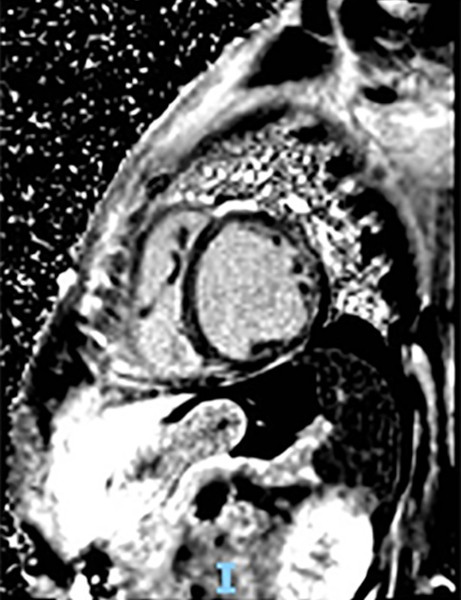

Figura 2

Resonancia magnética nuclear cardíaca con gadolinio. Se observa realce mesocárdico que involucra el sitio de unión entre miocardio ventricular derecho e izquierdo y anteroseptal e inferoseptal, y patrón de realce subepicárdico anterolateral e inferolateral.

En UCO se indica balance hídrico negativo; pulso de levosimendan; y se inicia tratamiento médico completo para insuficiencia cardíaca avanzada. Durante la internación se realiza ecocardiograma con medición de strain (- 14 %); angiotomografía computada coronaria con score de calcio donde no se evidencian lesiones; resonancia magnética nuclear (RMN) cardíaca con gadolinio que constata miocardiopatía dilatada con patrón de realce tardío mesocárdico que involucra el sitio de unión entre miocardio ventricular derecho e izquierdo y anteroseptal e inferoseptal, además de realce subepicárdico anterolateral e inferolateral, patrón que también se encuentra descrito en otras entidades como la miocardiopatía dilatada idiopática y la miocarditis. Además se solicita ECG Holter de 24 hs que solo evidencia extrasistolia supraventricular de baja densidad. Luego de seis días de internación, se otorga el alta sanatorial con indicación de derivación a centro de trasplante de forma ambulatoria.